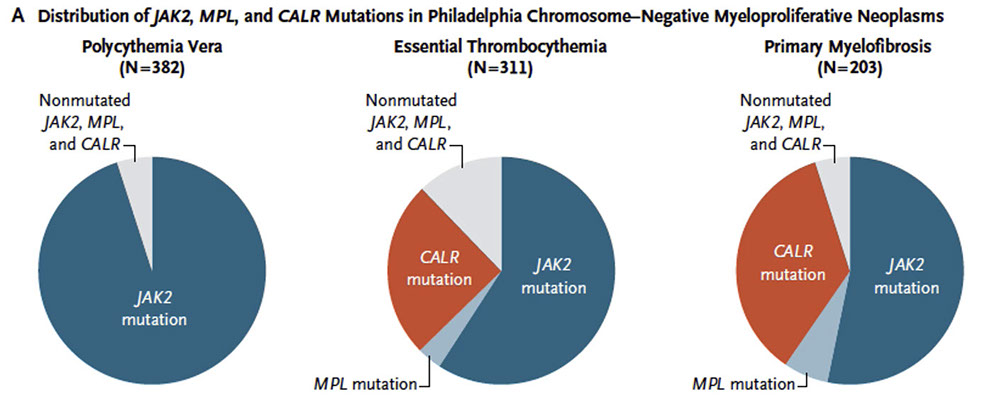

Molecular basis is JAK2 (Janus kinase 2) gene mutations (usually JAK2 V617F), >98% patients

JAK2 in >95% of PV patients, but is non-specific

Dz assoc c JAK2 gene mutations (~50% pts) and MPL and CALR gene mutations

- Disease associated with JAK2 gene mutations (~50% patients have them) and MPL and CALR gene mutations

~ Half have JAK2 V617F mutation

Mutation of the TROR receptor itself is due to mutations of the MPL gene, which encodes it [2], CALR is response for the folding of the MPL protein